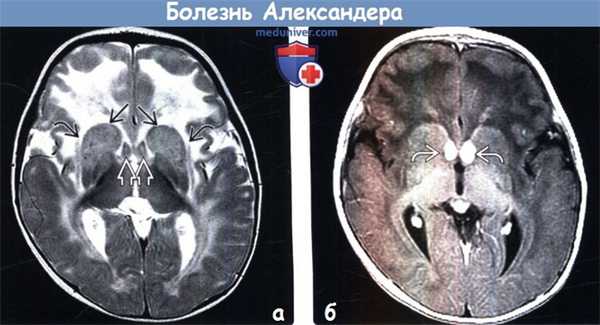

(а) Бесконтрастная КТ, аксиальный срез: определяется типичная картина при инфантильной форме болезни Александера (БА). Наблюдаются повышение плотности полосатого тела и гиперденсный перивентрикулярный ободок. Обратите внимание на симметричное снижение плотности от белою вещества (БВ) преимущественно лобных долей.

(б) МРТ, Т2-ВИ, аксиальный срез: определяются гипоинтенсивный узловой перивентрикулярный ободок в сочетании с симметричным легким повышением интенсивности сигнала от полосатого тела и таламуса. Кроме того, наблюдается диффузное повышение интенсивности сигнала от БВ большого мозга, наиболее выраженное в лобных долях, где область измененного сигнала простирается от стенок желудочков до субкортикальных U-волокон. (а) MPT, Т1-ВИ, аксиальный срез: визуализируется диффузно гиперинтенсивное, внешне отечное БВ - степень выраженности изменений нарастает от затылочных долей к лобным. Признаки миелинизации присутствуют только в БВ затылочных областей. Узловой перивентрикулярный ободок имеет гиперинтенсивный сигнал. Боковые желудочки аномально расширены.

(б) МРТ, постконтрастное Т1-ВИ, аксиальный срез: определяется контрастное усиление пери вентрикулярного ободка, головок хвостатых ядер и скорлупы билатерально. Узловая конфигурация перивентрикулярного ободка по типу «ушей кролика» является типичным признаком болезни Александера.

(а) Бесконтрастная КТ, аксиальный срез: определяется отек, снижение плотности БВ больших полушарий с преобладанием в их лобных долях. На фоне гиподенсного БВ гиперденсный узловой перивентрикулярный ободок становится более заметным.

(б) МРТ, постконтрастное Т1-ВИ, корональный срез: определяется интенсивное контрастное усиление перивентрикулярных ободков в лобных областях и смежного БВ. Накопление контраста также отмечается по наружной поверхности головок хвостатых ядер, в скорлупе и своде мозга. Обратите внимание на симметричное снижение интенсивности сигнала от отечного БВ лобных и височных долей.

(а) МРТ, Т2-ВИ, аксиальный срез: при более запущенной форме заболевания наблюдается симметричное повышение интенсивности сигнала от БВ больших полушарий и глубоких серых структур с наибольшей выраженностью в лобных долях и области полосатых тел. Обратите внимание на набухание головок хвостатых ядер, а также свода мозга. Зоны повышения интенсивности сигнала распространяются на наружные и крайние капсулы, на фоне чего выделяется ограда мозга.

(б) МРТ, постконтрастное Т1 -ВИ, аксиальный срез: у этого же пациента определяется высокоинтенсивное контрастирование свода мозга и слабоинтенсивное контрастирование поверхности головок хвостатых ядер.